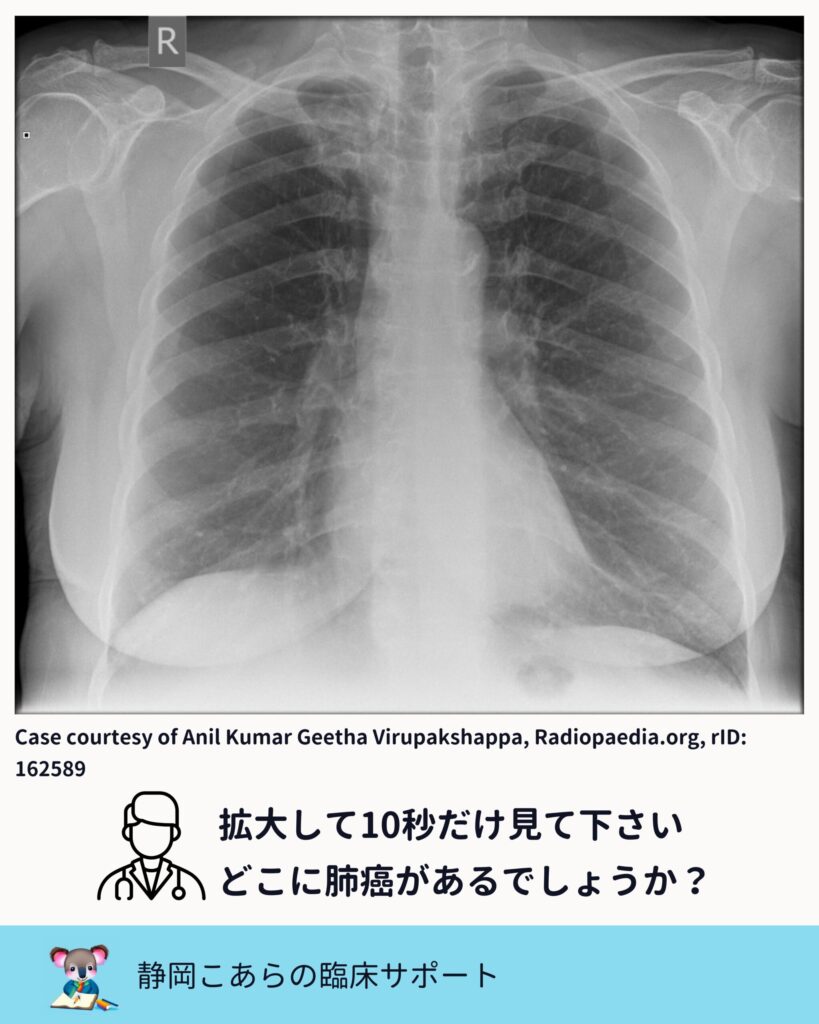

胸部レントゲンで肺癌が見えにくい部位は、

古くからいくつか指摘されています。

・心陰影と重なる部位

・肺尖部

・鎖骨と重なる部位

・肺門部

・肋骨や横隔膜と重なる部位

これは教科書的な知識であり、

Radiopaedia などの症例集を見ても繰り返し示されています。